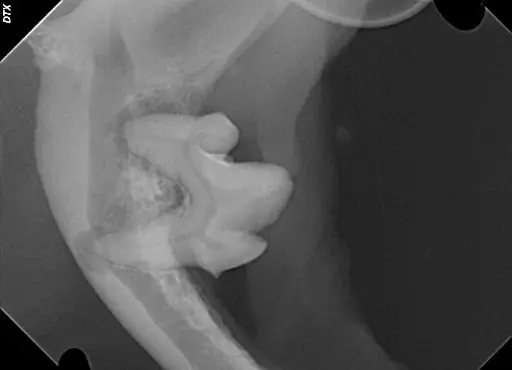

Figure 4 – A mandibular molar with severe periodontal disease that has progressed all the way to the tip of each root. Note the absence of all other local teeth that have already been lost to periodontal infection.